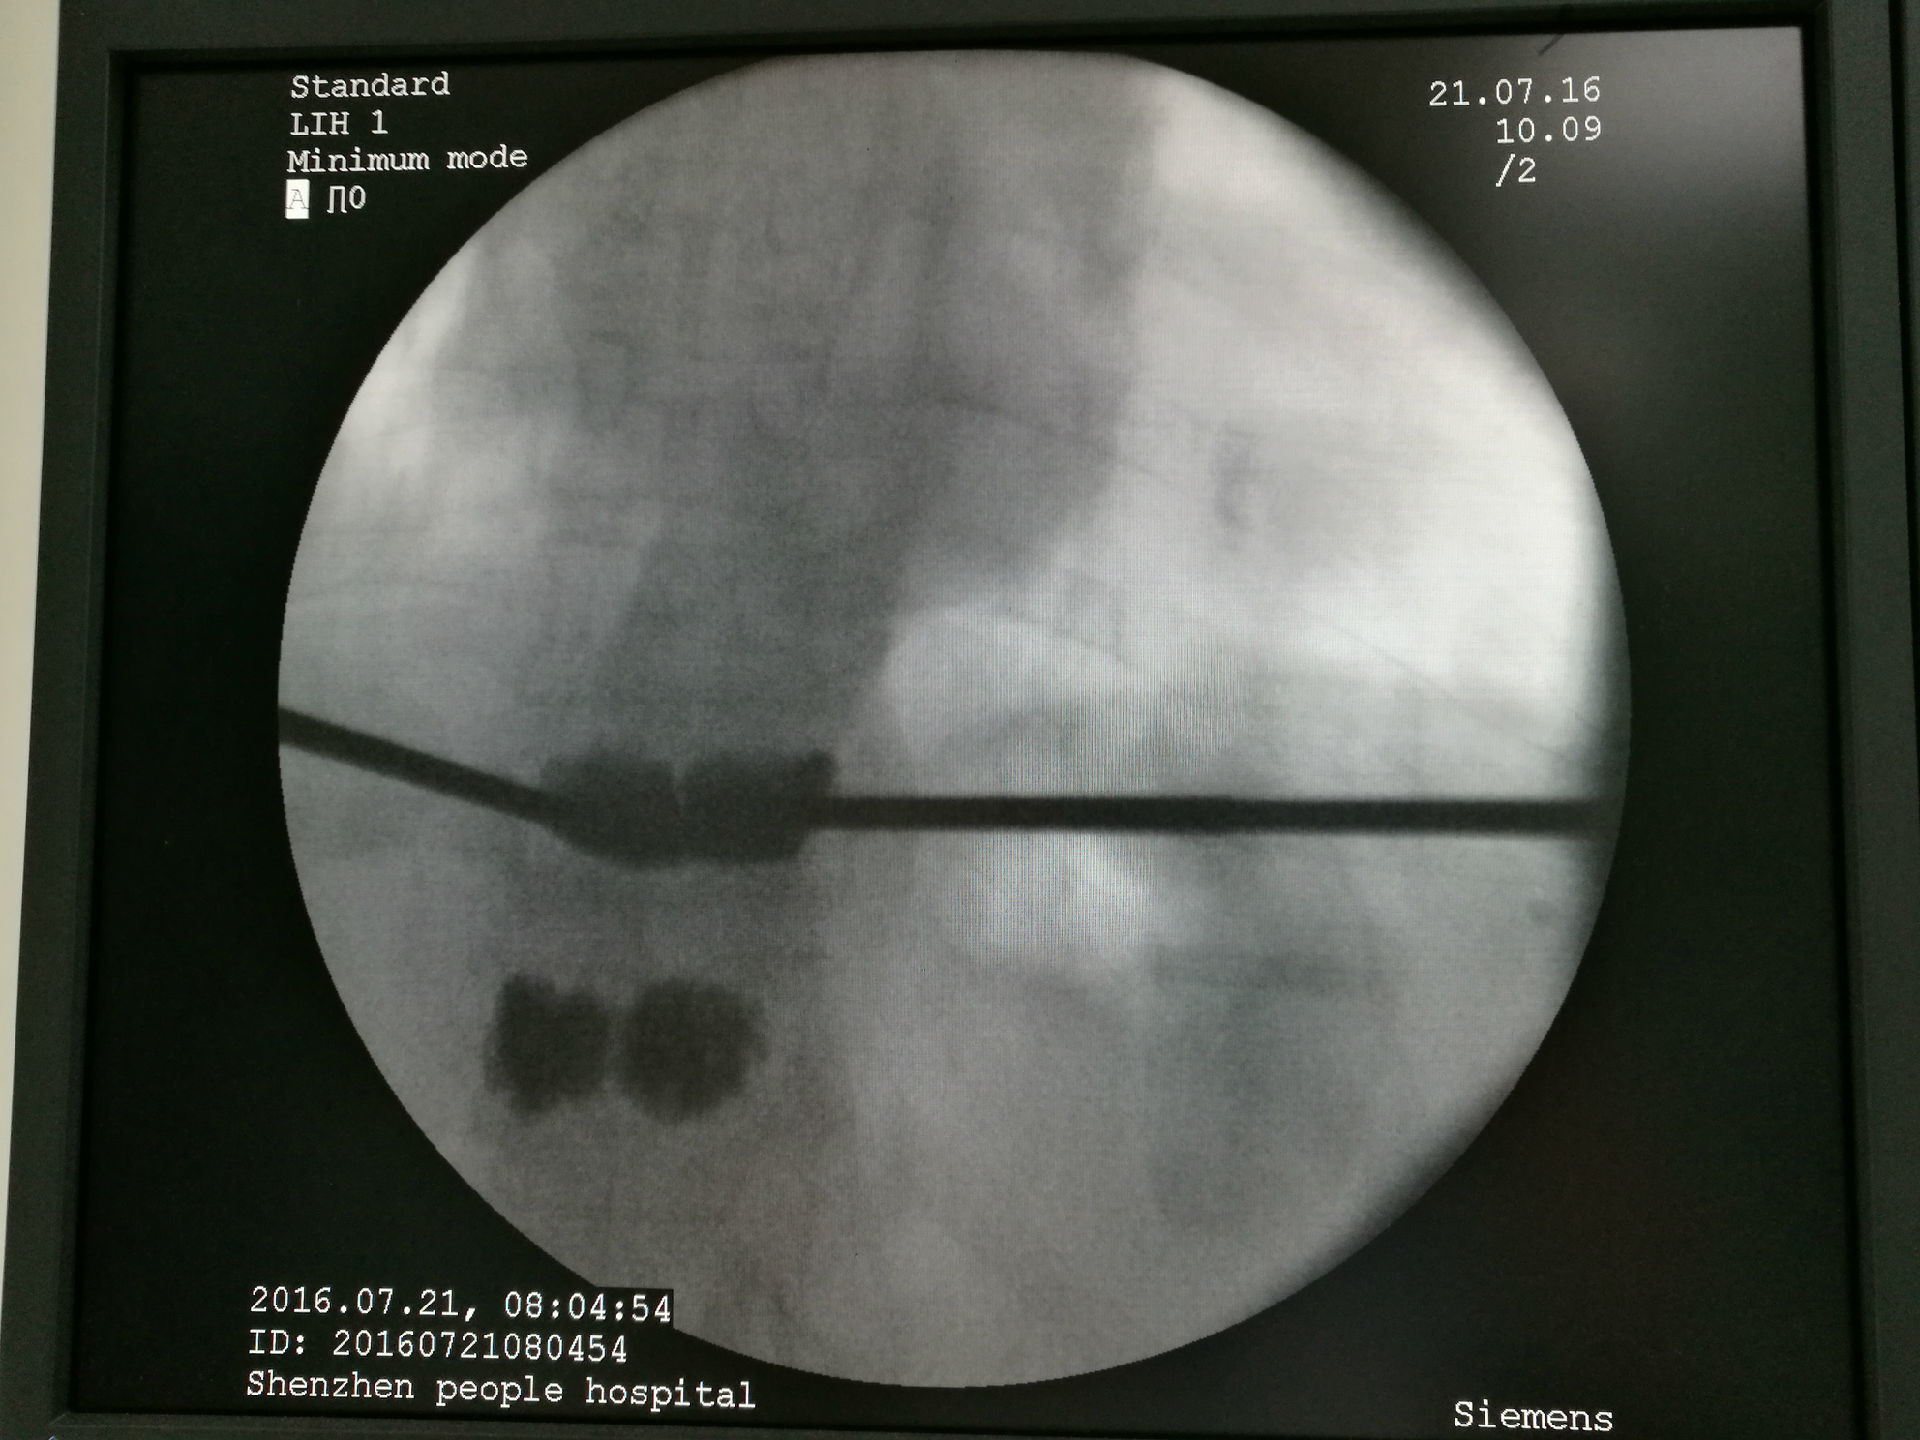

陈XX,女性,62岁,4年前因骨质疏松导致胸12骨折,在外院行微创椎体骨水泥手术,术后患者未规律抗骨质疏松药物治疗,1月前出现胸腰背痛,外院MRI提示胸11椎体(邻椎)发生新鲜压缩性骨折,在我院行微创椎体成形术,术后胸腰背痛明显缓解。